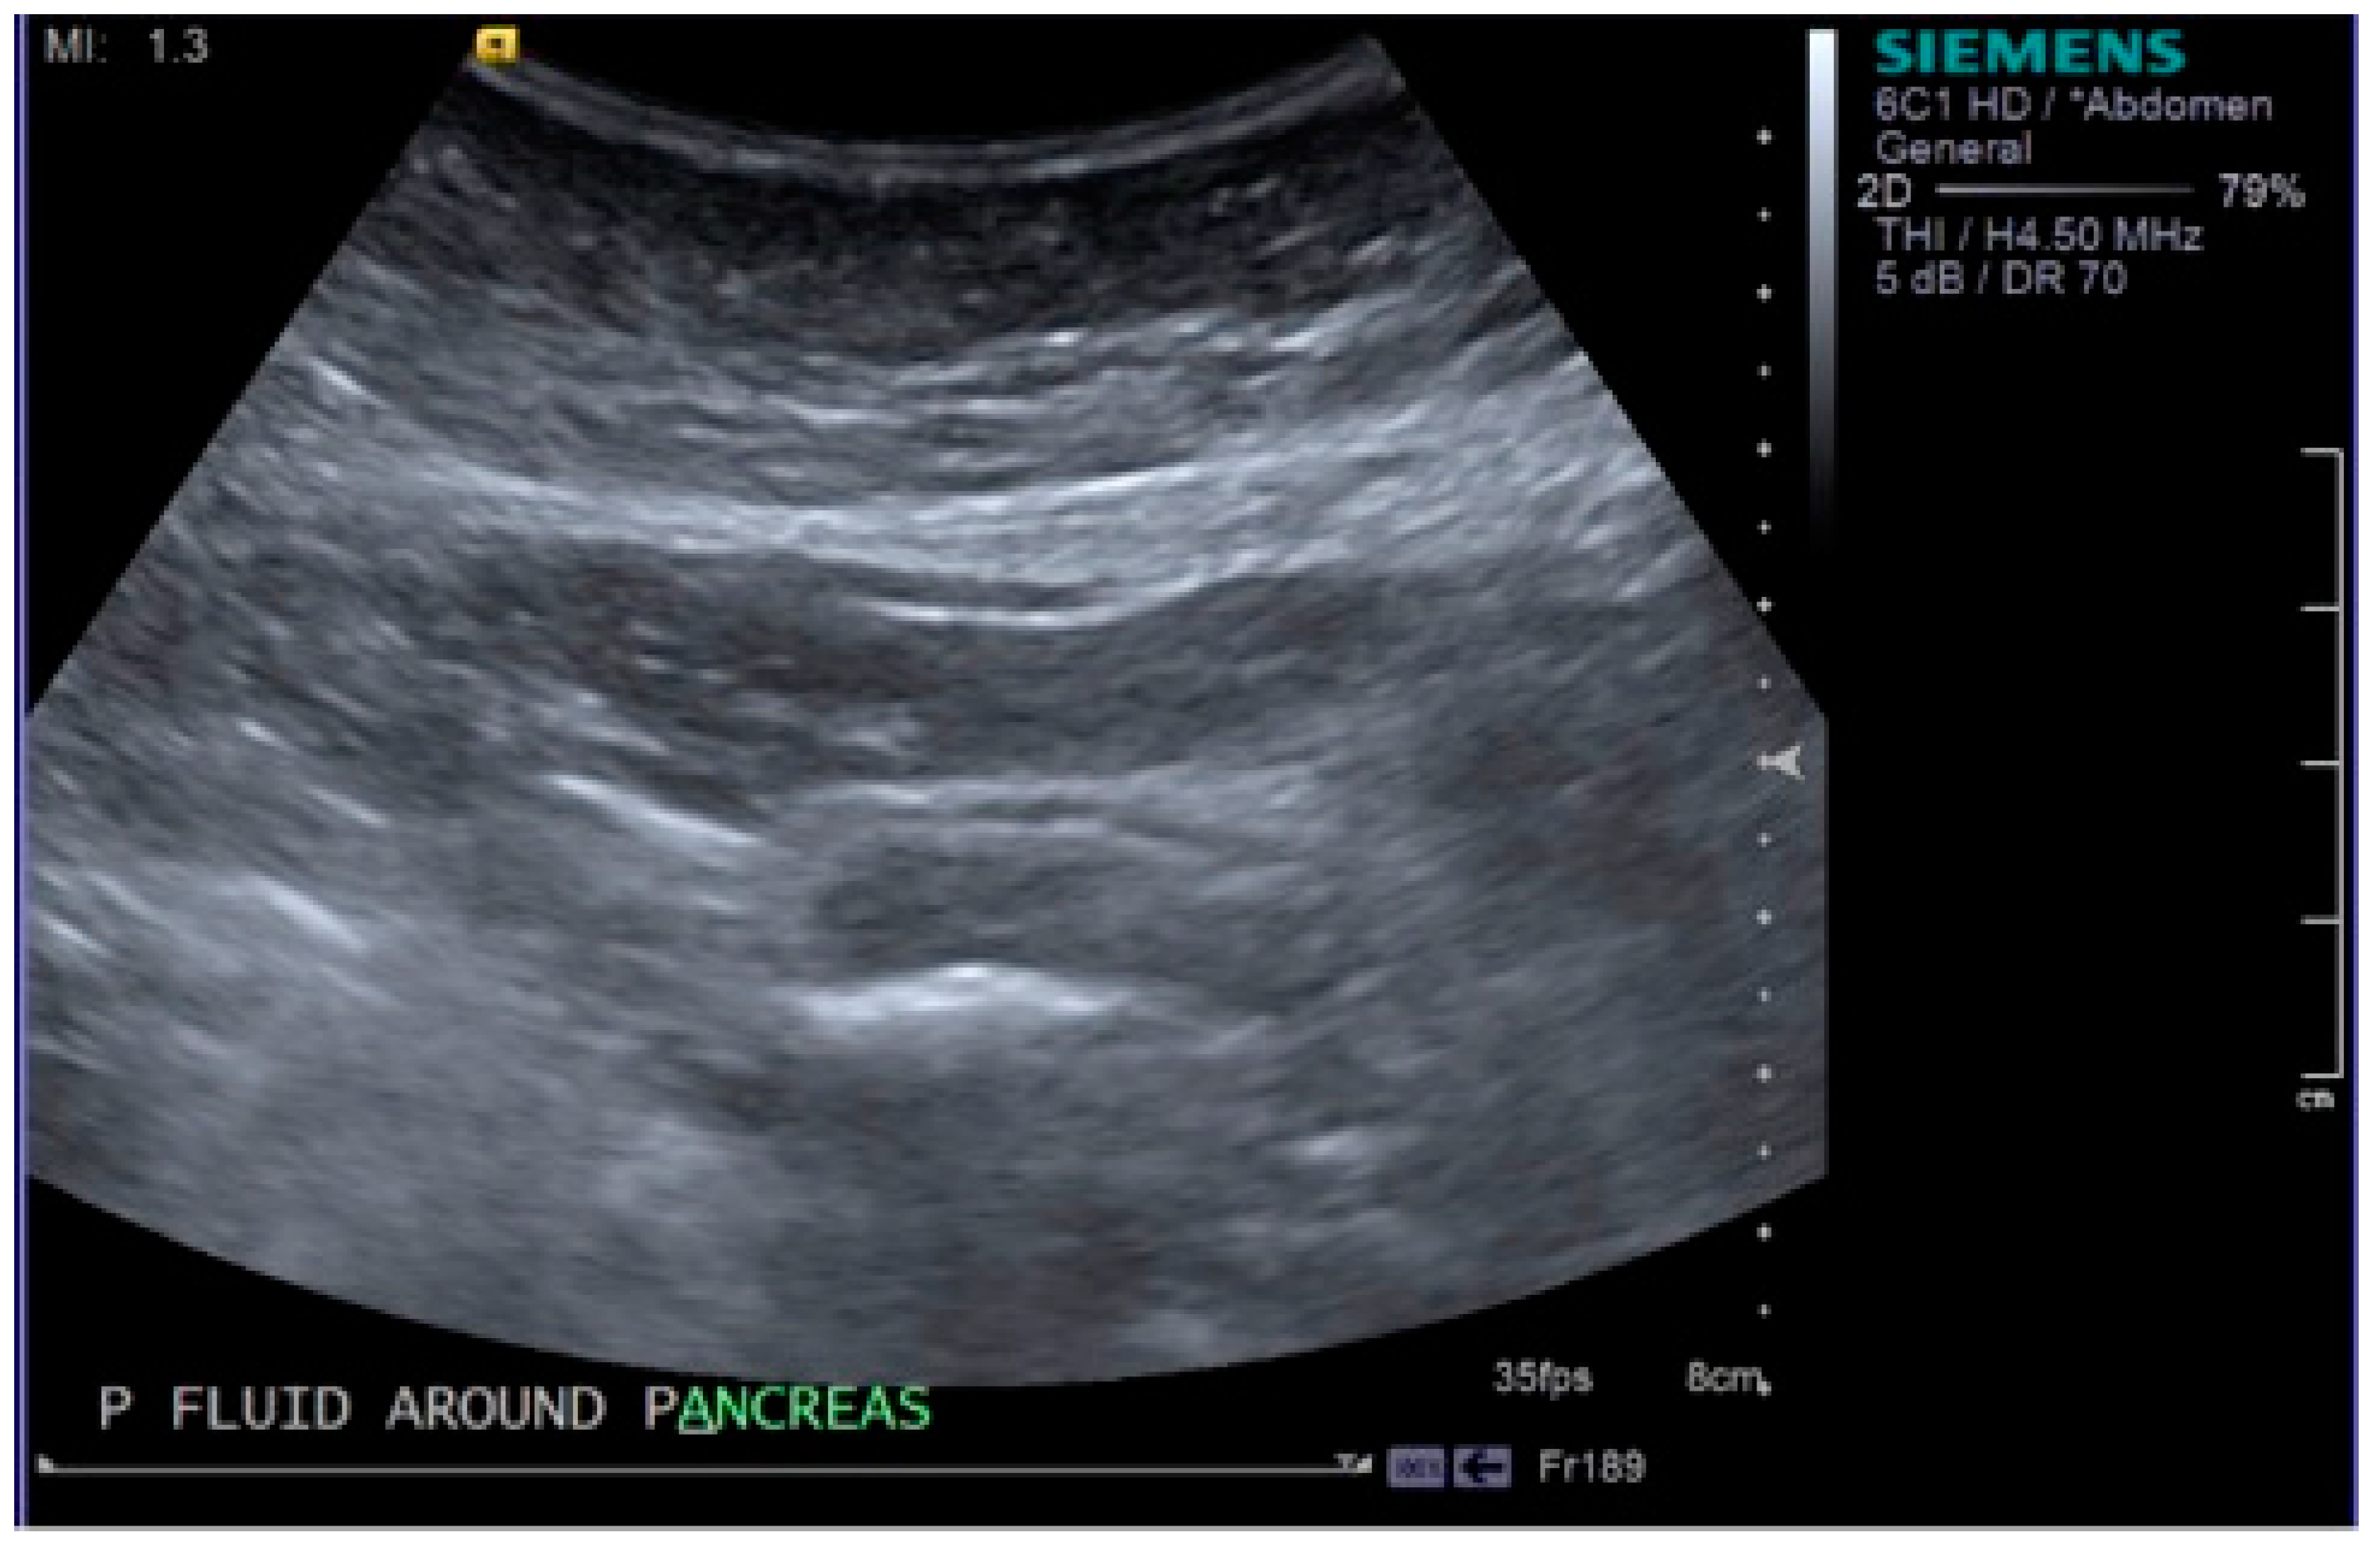

Intravenous access was obtained and blood tests taken. The patient was commenced on intravenous fluids, intravenous antibiotics and further analgesia before being admitted to the surgical triage unit. Initial blood results showed a haemoglobin (Hb) of 108 g/L, which was around the patient’s baseline. Bilirubin 185 µmol/L, alanine transaminase (ALT) 301 IU/L, alkaline phosphatase (ALP) 140 IU/L, amylase 3308 IU/L, c-reactive protein (CRP) 6 mg/L, white blood cells (WBC) 16.9 × 109/L and lactate dehydrogenase (LDH) 1085 IU/L. Urea and electrolytes, calcium and lactate were all normal. The blood results in addition to the clinical picture demonstrated an obstructive jaundice and acute pancreatitis, possibly secondary to gallstones. The patient scored a 2 on the Glasgow score [7]. Shortly following admission, the patient was requiring oxygen with an increase in all over body pain and further pyrexia. Observations were as follows; temperature 40 °C, heart rate 114 bpm, blood pressure 146/85, respiratory rate 22, saturating 100% on 4 L of oxygen. An ultrasound scan (USS) was obtained confirming acute pancreatitis with a dilated gallbladder containing dense debris and small calculi (Figure 1 and Figure 2). The common bile duct (CBD) measured 7 mm. Moderate pleural effusion on the right, small pleural effusion on the left. Repeat blood tests showed a Hb of 67 g/L, reticulocytes 3.4%, bilirubin 307 µmol/L, ALT 301 IU/L, ALP 121 IU/L, CRP 48 mg/L, WBC 9.7 × 109/L.

Figure 1.

Image taken from the ultrasound scan demonstrating areas of fluid around the pancreas, confirming acute pancreatitis.